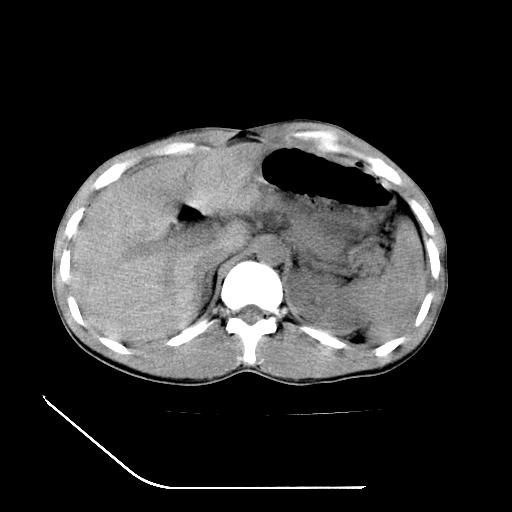

m-25y 高空堕落 12 月5号

12月7号病人尿量200ml/24h 急查双肾ct

左肾挫裂伤并肾周血肿;

肝肾间隙可见液区,建议手术探查;

左肾挫裂伤并肾周血肿

支持 : 左肾挫裂伤并肾周血肿

支持:1、左肾挫裂伤并肾周血肿;

2、少量腹水;

3、左肾旋转不良;

4、反射性肠淤张。

除了1:左肾挫裂伤并肾周血肿;

2:少量腹水

第二次ct检查后:临床医生腹水穿刺后考虑肠系膜动脉破裂,后实行剖腹探查:于空肠距离十二指肠90cm处发现肠管破裂,破裂口较小;修补后关腹。